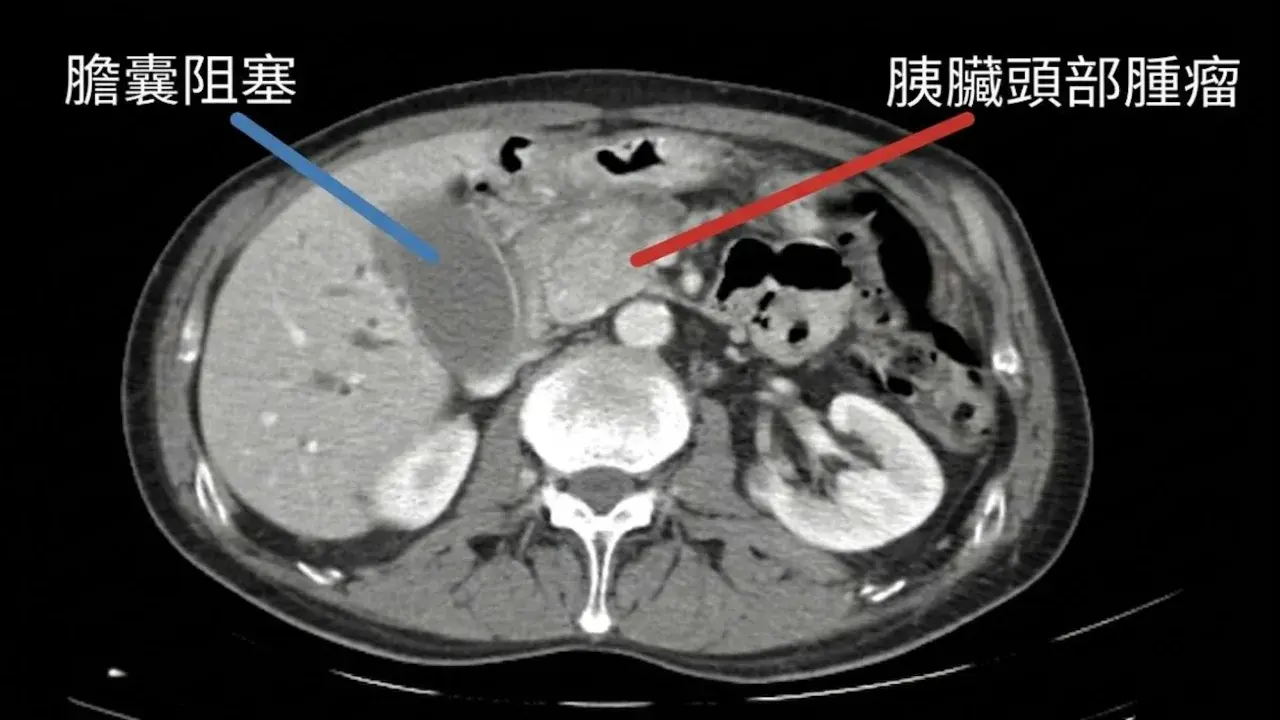

ผลการตรวจร่างกายพบว่าเธอมีก้อนเนื้อขนาด 4 เซนติเมตรที่ ส่วนหัวของตับอ่อน ซึ่งก้อนเนื้อนี้ไปกดทับท่อน้ำดี ทำให้น้ำดีไหลย้อนกลับเข้าสู่กระแสเลือดจนเกิดอาการดีซ่านอย่างรุนแรง